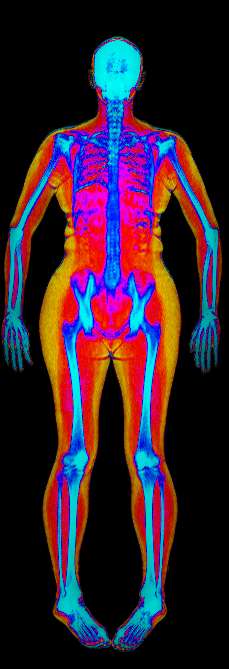

DEXA Scan Visceral Fat

Fat

Lean

Bone

Visceral fat, sometimes called "spillover" fat, builds up around internal organs like the liver and pancreas once subcutaneous fat stores are full.

While some is protective, too much increases the risk of heart disease and diabetes.

A healthy measurement for you would be < 100cm².

Your Visceral fat measurement is 58.8cm²

Normal risk for metabolic disorders, cardiovascular diseases